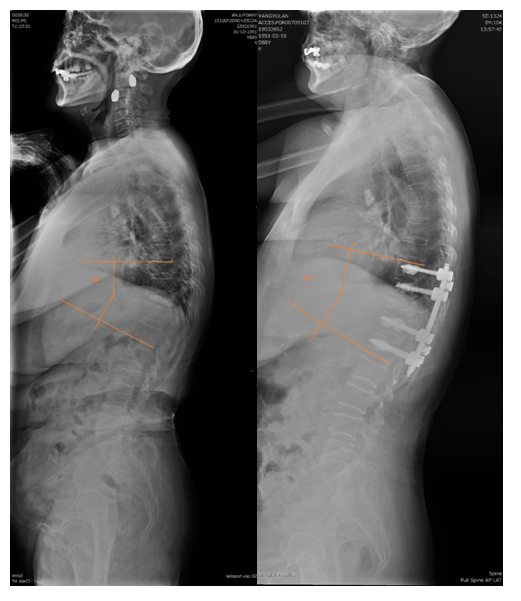

术前X线

俯卧过伸位片

术后影像学

术后X线

术前后侧位

术后3月X光